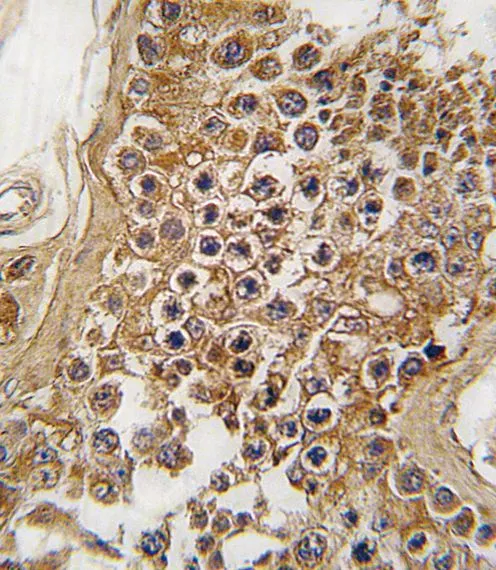

ALK抗体, Internal

目录号 GTX81366

实验应用WB IHC-P

种属反应Human